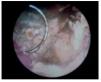

Imagen 1.Cistoscopia de control observándose una lesión intravesical en el sitio de resección tumoral previa.

Presentamos el caso de un paciente masculino de 62 años de edad con antecedente de tabaquismo de 20 cigarros por día durante 20 años. Un año y cuatro meses previos a su padecimiento actual, presentó cuadro de hematuria macroscópica con diagnóstico posterior de carcinoma papilar de células transicionales el cuál se manejó con resección transuretral de tumor vesical encontrándose en estadio Ta, agregándose quimioterapia intravesical con mitomicina C. Inició su padecimiento actual con sintomatología irritativa intermitente tras terminar con el ciclo de terapia intravesical con mitomicina C, manejándose con fluroquinolonas, no remitiendo sintomatología. El examen general de orina reportaba: pH de siete, leucocituria y microhematuria con urocultivo estéril, el resto de sus laboratorios se encontraban normales, se realizó (Figura 1), se decidió completar protocolo de estudio con urografía excretora y tomografía axial computada (Figura 2) programándose resección transuretral de lesión intravesical (Figura 3). Durante la cirugía se encontró que la lesión se encontraba completamente adherida a la pared vesical, siendo difícil de resecar; contaba con bordes necróticos y tenía una consistencia pétrea al corte del asa, realizándose resección parcial de la lesión. En el examen de la muestra obtenida durante la cirugía y enviada a estudio patológico se reportó: depósito de cristales cálcicos con datos de cistitis crónica inespecífica. En el postoperatorio se manejó con cefalosporinas de tercera generación, aminoglucósidos y ácido ascórbico el cual se continuó por seis meses, no se demostró la presencia de Corynebacterium D2 en el cultivo específico. Se realizó un segundo procedimiento quirúrgico posterior a los seis meses, lográndose resección completa de la lesión, la cual se presentaba menos endurecida, realizándose control tomográfico (Figura 4), sin evidencia de calcificación a nivel vesical. Actualmente, el paciente se encuentra asintomático y con controles cistoscópicos que sólo muestran cicatrización vesical propia de sus antecedentes